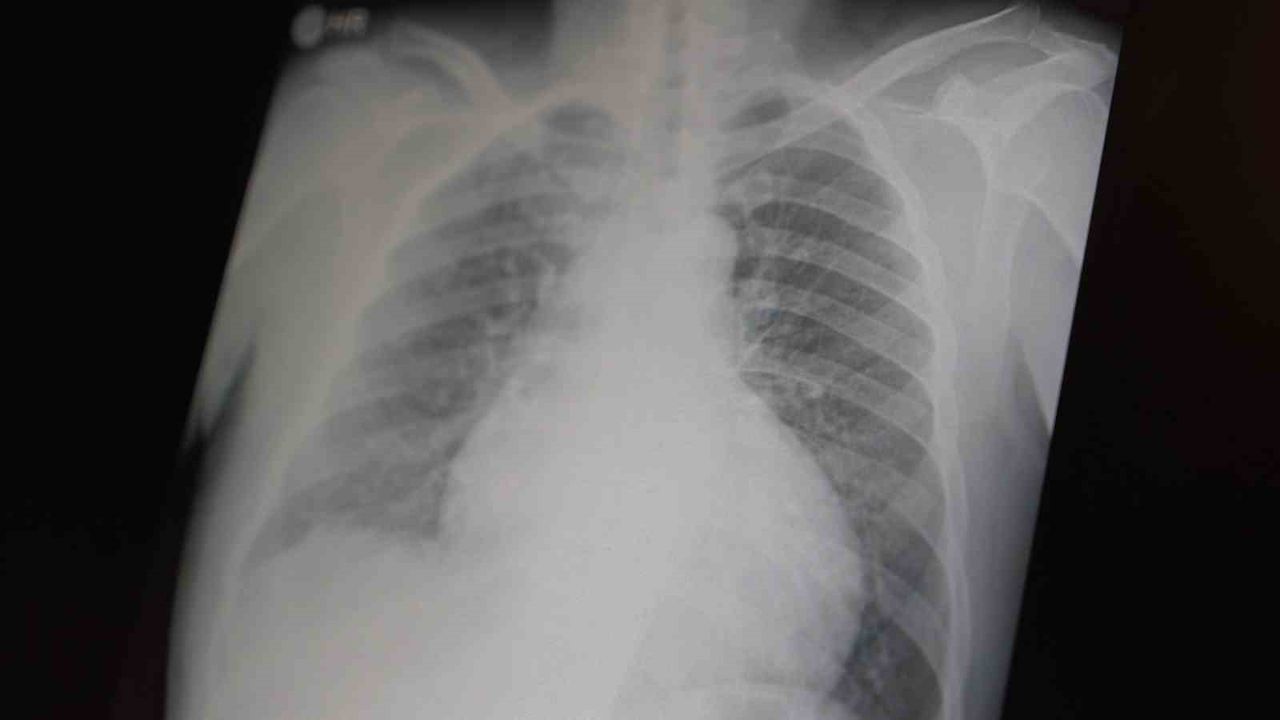

Prof. Dr. Şevket Özkaya, çocukları ve gençleri etkileyen bağımlılıklar hakkında açıklamalarda bulundu. Metamfetaminin sentetik bir uyuşturucu olduğunu ve kullanımının ölümcül sonuçlar doğurduğunu ifade eden Özkaya, 'Tüm dünyada çocukları ve gençleri etkileyen iki önemli bağımlılıktan bahsetmek istiyorum. Bunlar metamfetamin ve kokain bağımlılığıdır. Metamfetamin en ölümcül, en çok bağımlılık yapan, okul çağında en kolay ulaşılabilen bir sentetik uyuşturucudur. Kullanıma bağlı ciddi akciğer ve karaciğer sorunları ortaya çıkıyor. Çok küçük dozlarda bile anında bağımlılık yapabiliyor ve tedaviyle bırakılması çok zor bir bağımlılıktır' dedi.

Açıklamalarında, her iki uyuşturucunun beyin hasarı oluşturduğunu ve nöro sinir hücrelerini harap ederek solunum ve kalbin durmasına sebep olduğunu vurgulayan Özkaya, 'Metamfetamin tüm dünyada bir sorun olmanın ötesinde, ülkemizde de gençlerimizi etkileyen toplumsal bir sorun olarak görülmelidir' ifadelerini kullandı.